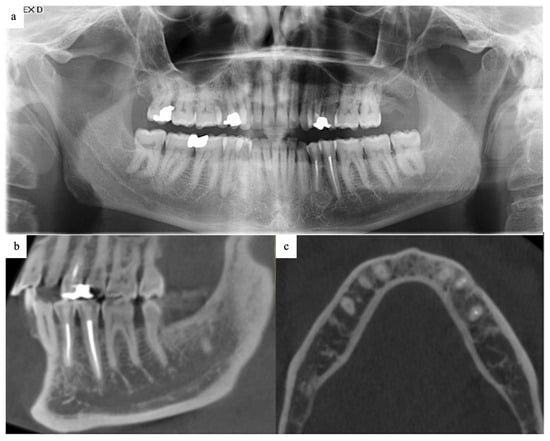

2.5. Follow-Up and Outcomes